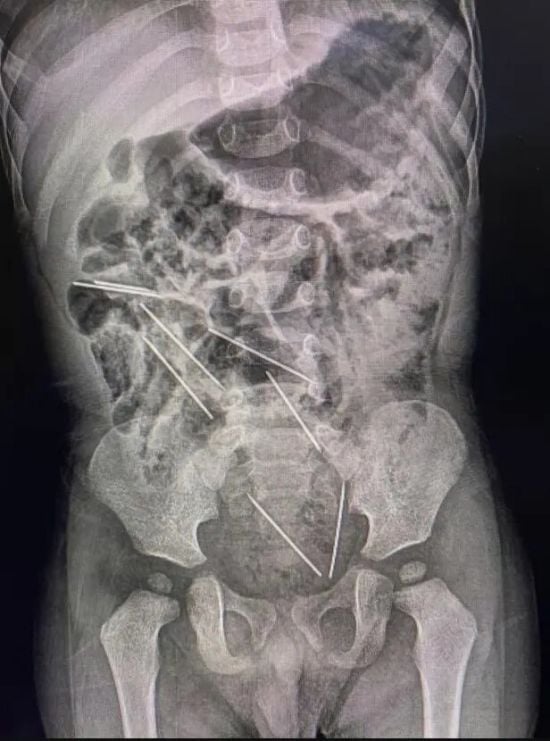

В Таджикистане в теле младенца нашли десять игл

Врачам уже удалось извлечь шесть игл, еще четыре находятся глубоко под кожей. Каким образом они могли попасть к ребенку, пока неизвестно. gazetavv.com »

Врачам уже удалось извлечь шесть игл, еще четыре находятся глубоко под кожей. Каким образом они могли попасть к ребенку, пока неизвестно. k.img.com.ua »

В Узбекистане в теле ребенка нашли 16 игл

В Узбекистане в теле 11-месячного младенца обнаружили 16 стальных игл для шитья. Предметы находились в толстой кишке, мочевом пузыре, внутри грудной клетки, шее, позвоночнике и сердце. По утверждению врачей, кто-то намеренно вонзал в ребенка иглы, пишет Kun. inforesist.org »